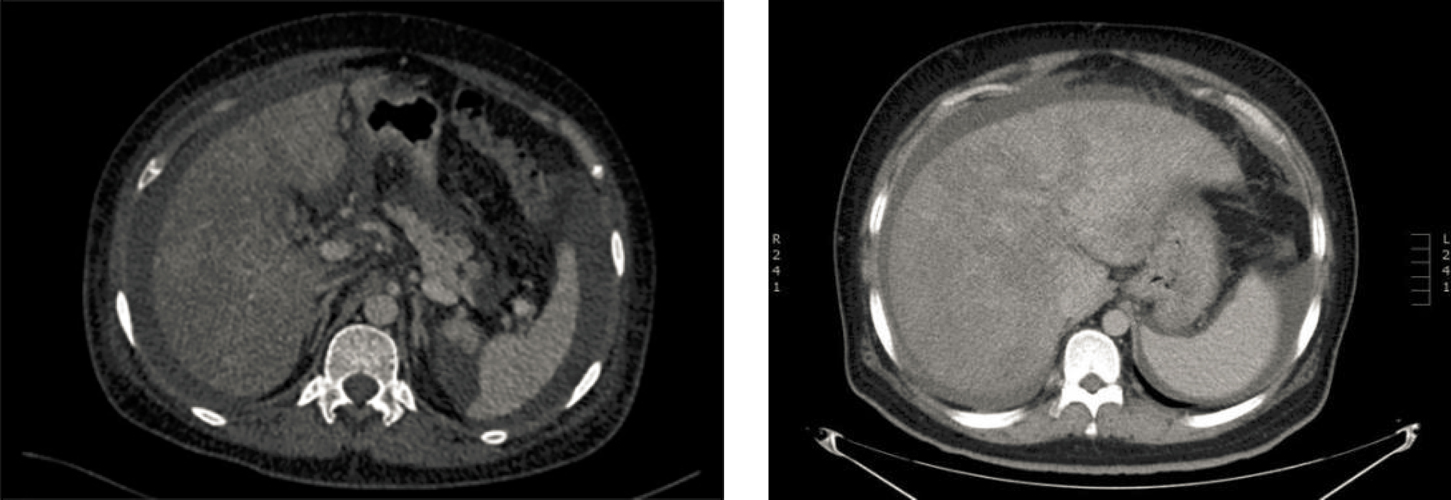

The study included 28 patients and excluded four patients with a previous history of alcohol consumption, two patients without follow-up data, and two patients with incomplete data. In total, 20 patients were enrolled, with 10 in the warfarin group and 10 in the rivaroxaban group. All patients ranged from 43 to 77 years of age, with seven males and 13 females. The patients were mainly taking Gynura segetum for low back pain, general health care, and other reasons. The daily dose was approximately 5–30 g, and the continuous duration during which it had been taken was 2 weeks to 2 years. There were two patients with hypertension and two with diabetes mellitus in both groups. Furthermore, there was one patient with a hepatic hemangioma in the rivaroxaban group, and one patient with a hepatic cyst in the warfarin group. In both groups, the hepatic parenchyma showed characteristic “map-like” and “patchy” nonuniform enhancement in the venous phase and balanced phases (Figure 1), the hepatic veins became thinner, the blood flow velocity slowed down and the elasticity increased significantly. All patients had ascites, and two patients each in the warfarin and rivaroxaban groups had umbilical vein opening. There were two patients with PVT in each group; two patients in the warfarin group and one patient in the rivaroxaban group had splenomegaly, while one patient in each group showed a decrease in liver volume and a disordered proportion of each lobe. The general characteristics of the study subjects and a comparison of the clinical data is shown in Table 1. There were no significant differences in age, sex, duration of taking Gynura segetum, biochemical indicators, or elasticity between the two groups (P > 0.05).

Figure 1: Enhanced Computed tomography scans showing “map-like” inhomogeneous enhancement of liver